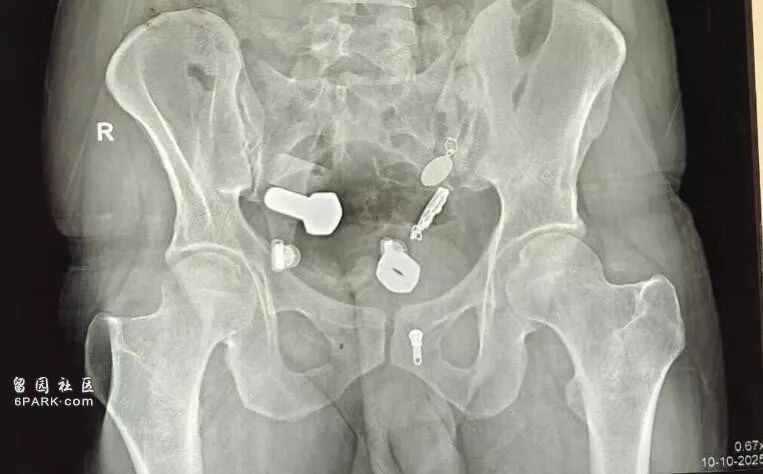

按常規流程,醫生給他開了影像學檢查,結果拍完片子,大家都驚呆了。

他的消化道簡直能開家伍金店:螺母、螺栓、金屬棒、鐵釘、別針......什麼都有,而且它們都已經隨腸胃運動來到了大腸裡,估計已經吞下很久了。

(醫學影像)